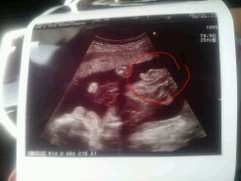

26W กำหนดคลอด 4 พ.ย. ค่ะ แม่ๆคนไหนได้ลูกชายบ้างค่ะ

ชายค่ะ ถ้าไม่หดกลับเข้าไปนะคะ😅

้ลูกชายตัวน้อย